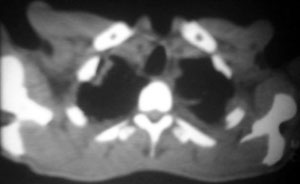

以下是引用逸风在2006-9-12 14:57:00的发言:[br]ct显示双肺上叶点片状及纤维索条状密度不均影,肺野外带近胸膜可见大小不等的含气空腔,壁略厚,境界清晰,未见液平面,中下肺野散在小片状及点状高密度影;纵隔内显示点状钙化,未见明显淋巴结肿大,构成胸廓诸骨未见明显异常.[br]诊断意见:1.双肺结核合并支气管播散;2.双肺上肺大泡.